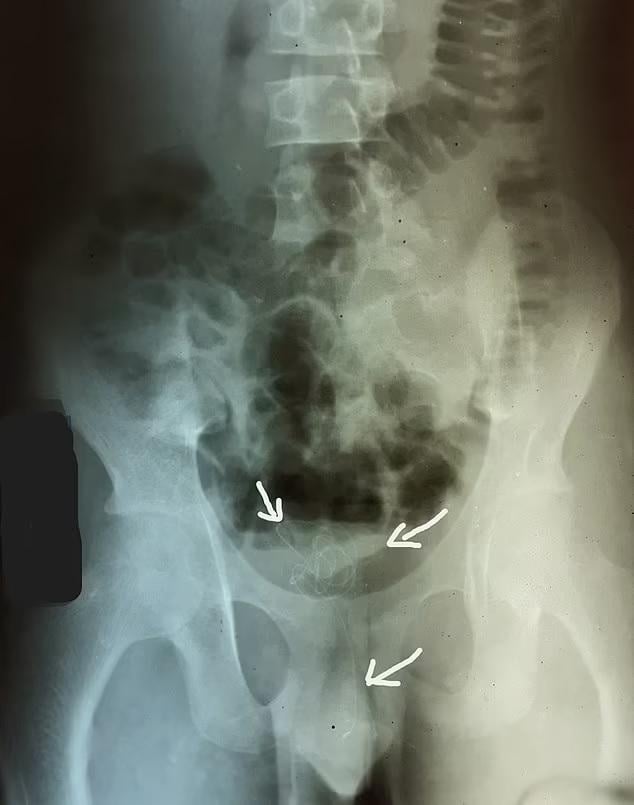

性上癮|日本老翁更嚇人90吋跳繩塞入陰莖

報道指,日本去年11月一個案更加嚇人,一名79歲老翁將90吋長的跳繩塞入陰莖,結果在膀胱內打圈塞住。由於要取出的難度極高,醫生甚至要靠電腦3D圖模擬如何在膀胱開刀取出跳繩。雖然老翁並沒有向醫生解釋為何塞繩入陰莖,但相信他是為了性快感。有英國醫生說,這是他聽過最極端的個案。